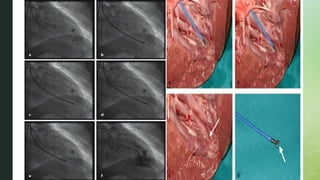

IMAGING GUIDANCE

 EMB is mostly performed under fluoroscopic guidance.

 Pre procedural imaging like echo, cardiac MRI, PET can be used to direct

site specific EMB

 Procedural imaging like echocardiography can be performed simultaneously

with fluoroscopy to improve the accuracy of the EMB procedure.

 Intracardiac echo has also been successfully used to guide EMB of cardiac

tumours.

 Electroanatomic voltage mapping is being used in diseases with focal

pattern associated with VT ( sarcoidosis ), it is further facilitated with 3 D

mapping.